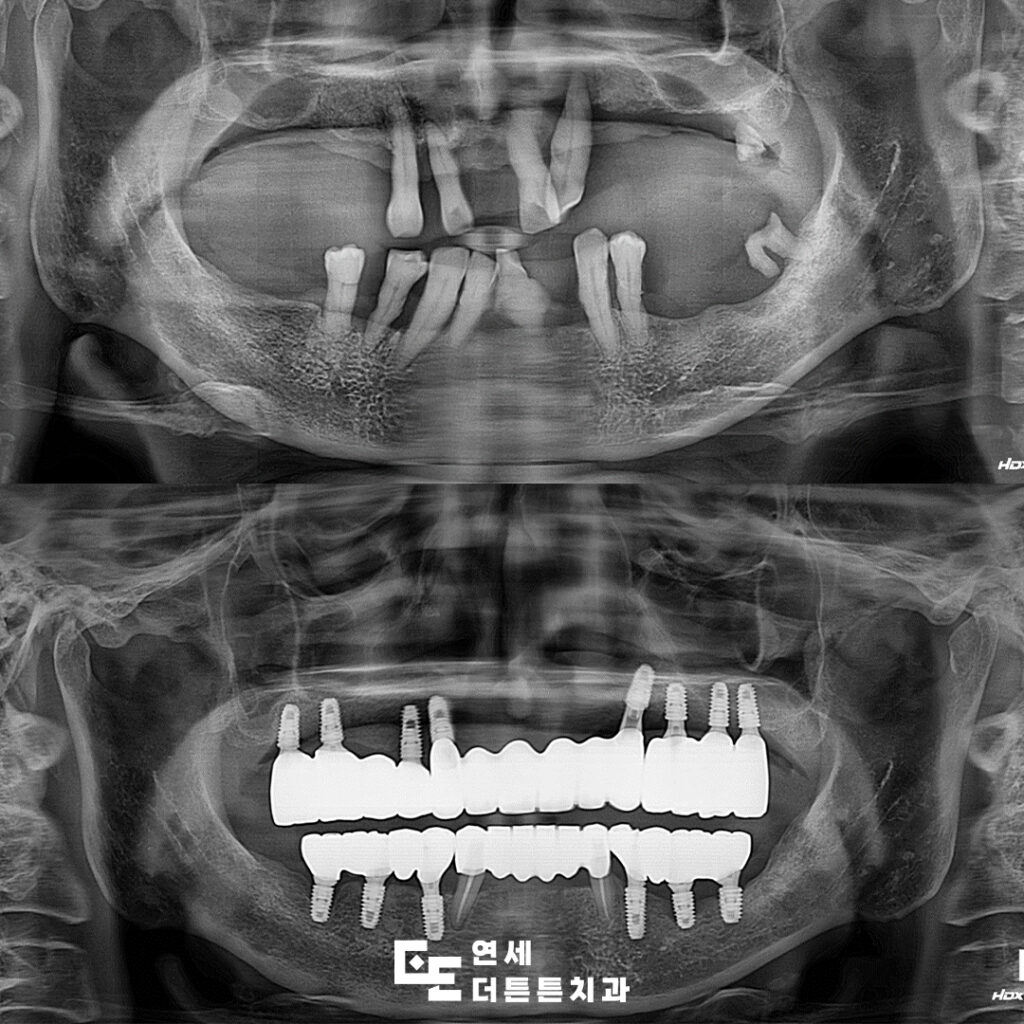

환자분의 사진을 보시면

오랜 기간 진행된 치주염으로 인해

잇몸뼈가 많이 녹아 있고 뿌리만 남아 있는

치아들도 곳곳에서 관찰되고 있었는데요.

정상적인 치아의 뿌리는 잇몸에

담겨 있는 것처럼 뼈 깊숙이 고정되어 있는데요.

환자분의 경우에는 뿌리를 잡고 있는

잇몸뼈가 거의 다 녹아 치아가 많이 흔들리고

상태가 좋지 않았습니다.

따라서, 살려 쓸 수 있는 치아 2개 정도를

제외하고 모두 발치 후 망월사역치과 전체임플란트를

진행하시기로 하였습니다.

양쪽 아래 송곳니 두 개는

신경치료 후 크라운을 진행하고

나머지는 모두 임플란트를 진행하였습니다.